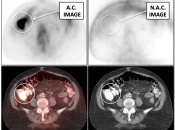

Value of Non-Attenuation Corrected (NAC) Images

Resolving Attenuation Correction Artifacts:

The CT images obtained during an exam are not only used for “anatomic” interpretation. They are also used for “attenuation correction” (AC) of the PET images, generating the much more useful AC PET images used for interpretation.

Unfortunately, attenuation correction of PET images can result in falsely elevated metabolic activity in regions of high CT density (e.g. metallic devices, oral contrast, calcification).

In such cases, these areas must be reviewed on the NAC (non-attenuation correction) images. If these regions are not also hypermetabolic on the NAC images, then their apparent increased FDG-uptake on the AC images is artefactual.

This phenomenon is almost exclusively seen with older PET/CT scanners, as most modern scanners utilize newer algorithms that do not “over-correct” in these areas of increased density.